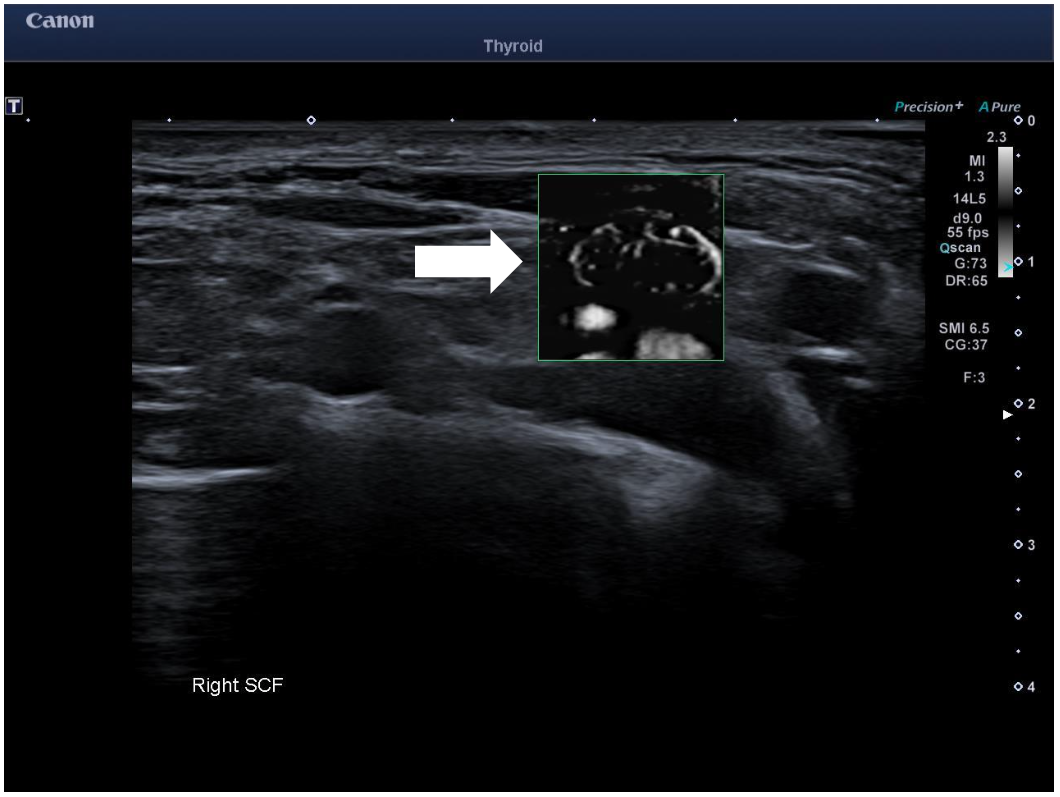

Owing to the aggressive cancer in a young patient, a staging PET/CT study was performed which showed a small but metabolically active lymph node in the right supraclavicular fossa. An US of the supraclavicular fossa revealed several small volume nodes. The most prominent 10 x 4 mm node had a normal architecture but with only mild cortical thickening. Power Doppler imaging (PDI) and color Doppler imaging (CDI) showed feeding vessels but otherwise no suspicious features. However, on using Superb Microvascular Imaging monochrome (SMI), this revealed abnormal peripheral vascularity which was best depicted in the monochrome mode. This feature made the node suspicious for malignancy and corresponded to the FDG avid node on the PET study. Subsequent fine needle aspirate of the right supraclavicular node confirmed metastatic disease.

Longitudinal ultrasound of right supraclavicular fossa showed a small 10 x 4 mm lymph node in the right supraclavicular fossa (SCF) with mild cortical thickening. SMI revealed abnormal peripheral vascularity which made it suspicious for metastatic infiltration and most likely represented the metabolically active SCF node on the recent PET imaging.

Clinical perspective: PDI and CDI ultrasound showed relatively normal vascularity in the SCF Lymph node, however, SMI, particularly monochrome mode, outlined clearly the abnormal peripheral vascularity which allowed FNA of the correct “small” node which was FDG avid on the PET study . A recent study has shown SMI yields more detailed information about nodal vessel when compared to PDUS and can be useful in differentiating between malignant and benign lymph nodes.